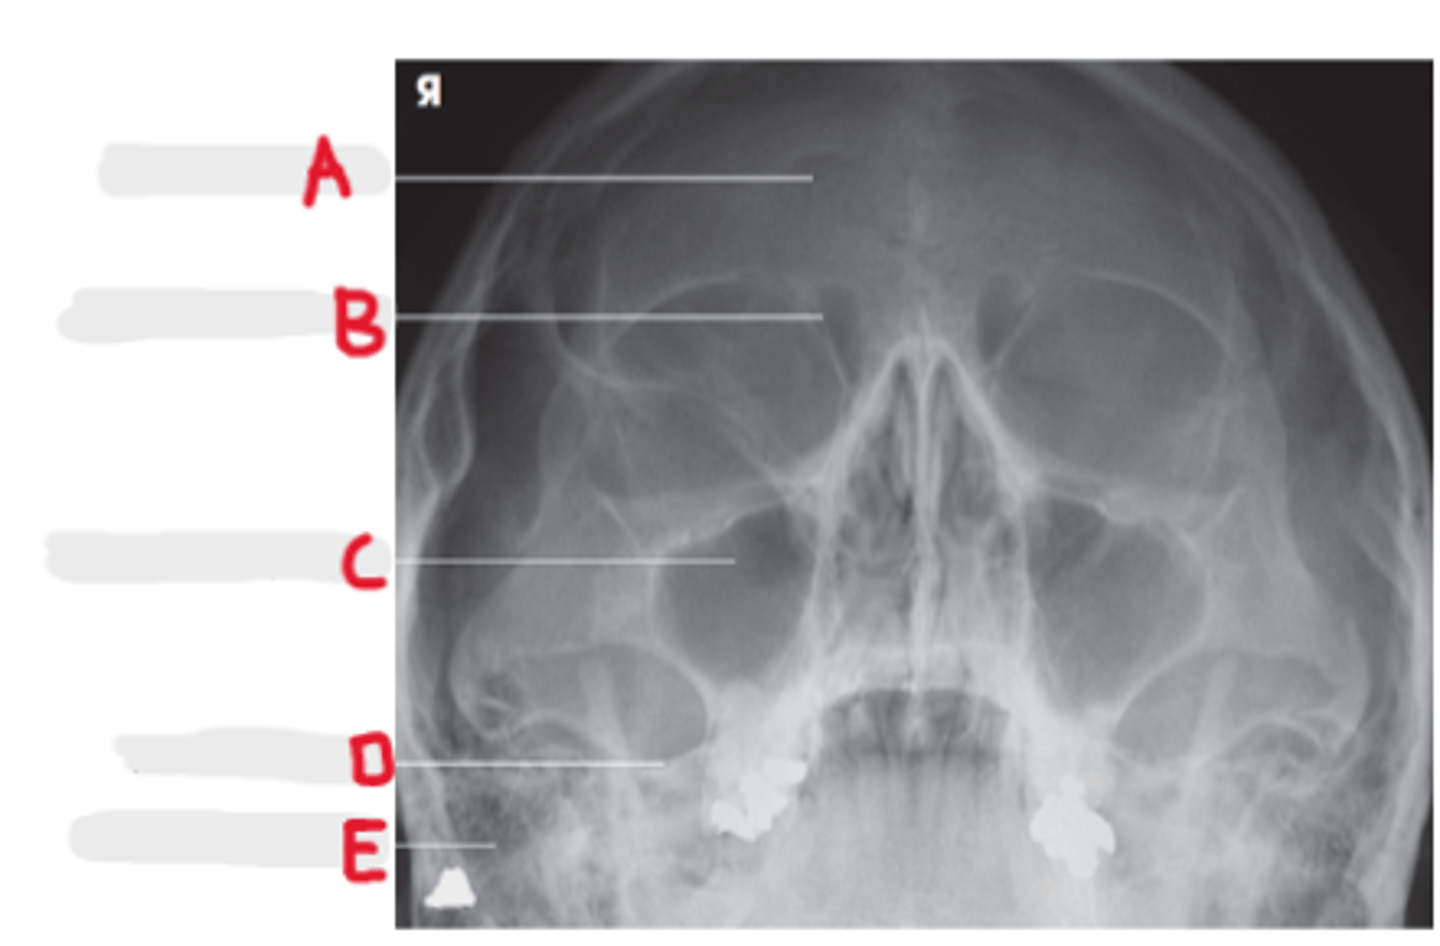

PA axial (Caldwell Method)

What projection is this?

CR exits the nasion & 15 degree caudal angle

What is the CR for PA axial (Caldwell Method)?

OML perpendicular to IR

What line should be perpendicular to the IR for a PA axial (Caldwell Method)?

Interpupillary line (IPL)

What line is parallel to the IR for a PA axial (Caldwell Method)?

Frontal and Ethmoid

What sinuses are clearly demonstrated on the PA axial (Caldwell Method)?

Lower 1/3 of orbits

Where are the petrous ridges located in a PA axial (Caldwell Method) radiograph?

Frontal Sinuses

A

Ethmoid Sinuses

B

Maxillary Sinus

C

Petrous ridge

D

Mastoid air cells

E